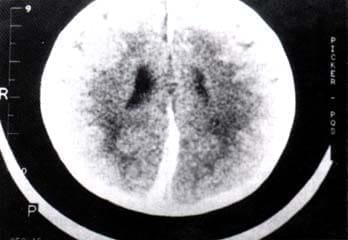

TAC cerebral muestra fractura conminuta témporo-pariero-occipital derecho con múltiples contusiones hemorrágicas intraparenquimatosas mayores en el hemisferio derecho, con efecto de masa leve, con desplazamiento de la línea media y edema cerebral difuso.

Figura No. 1.

La TAC cerebral muestra hematomas subdurales agudos, uno laminar frontal izquierdo, otro parasagital frontoparieto-occipital izquierdo de más o menos 1.5 cm de su parte más ancha (frontal posterior) con moderado afecto comprensivo local y otro parasagital occipital derecho. Figuras No. 3 y No. 4.

Figura No 3. Figura No. 4.